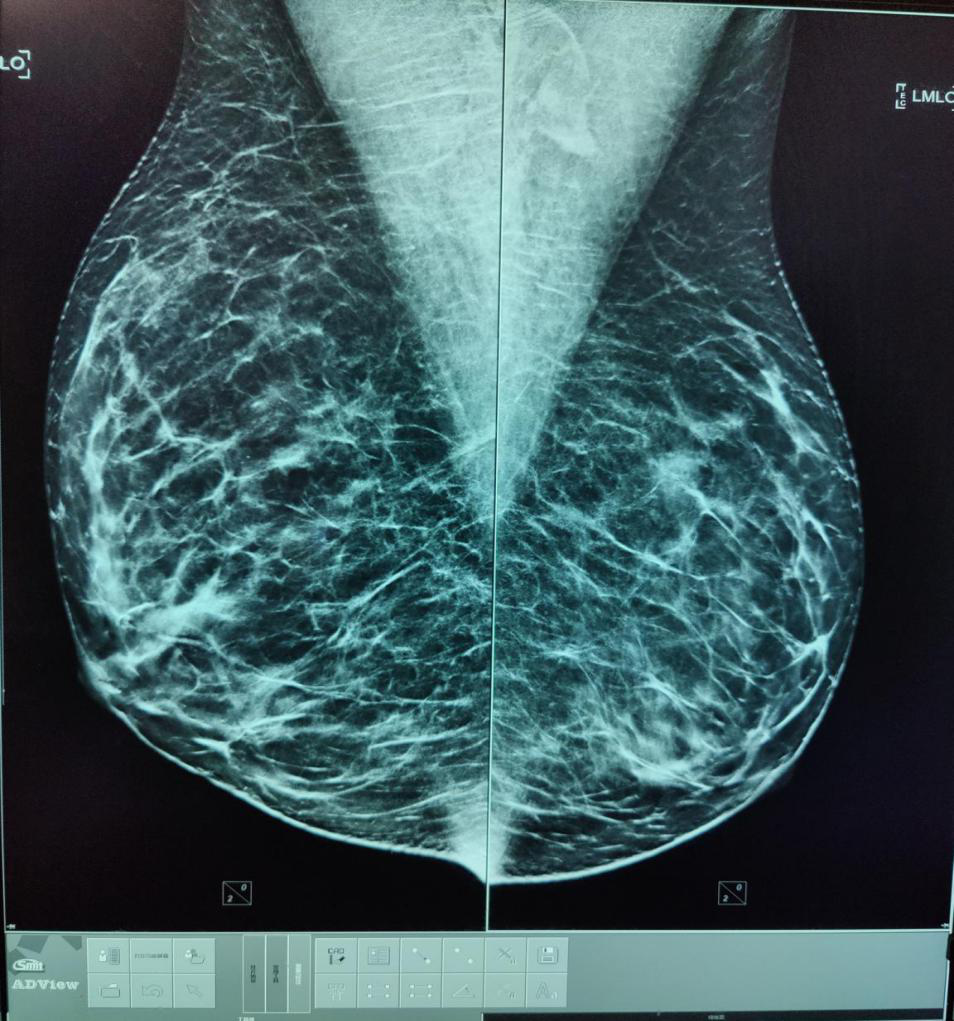

4月18日,集“筛查、诊断、3D定位活检穿刺”三个高端功能于一体的美国豪洛捷智能3D数字化乳腺X线摄影系统在玉溪市中医医院投入使用。

采用业内分辨率最高的非晶硒探测器,空间分辨率≥71p/mm,像素大小≤70um。

断层+传统2D乳腺摄影、断层+合成2D乳腺摄影、断层+传统2D+合成2D乳腺摄影三种成像模式,能够最大限度的显示乳腺细微结构及病变。

配备专业乳腺诊断工作站,工作站竖屏为分辨率达2KX2.5K的Barco医用专业灰阶竖屏屏,搭载豪洛捷数字化乳腺影像计算机辅助侦测系统(CAD),能很大程度避免乳腺钙化、肿块的漏诊。

美国FDA认定其为致密型乳腺的优选检查方法,其数字化乳腺断层摄影技术(digital breast tomosynthesis DBT)简称TOMO技术,是乳腺癌筛查首选的检查方法。

传统乳腺钼靶检查中,腺体组织会不同程度遮蔽病灶,而数字乳腺断层摄影可以通过对乳腺不同角度的多次摄影获取信息,有效区分正常腺体组织与病灶,更好发现一些隐匿的微小病变,并且对病变的边缘、边界显示清晰,可以提供更多的细节信息帮助对病变性质的判断。与此同时,TOMO技术并不增加射线剂量,患者可以放心接受这项检查。